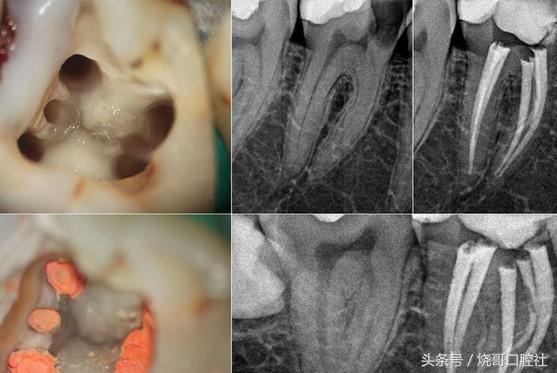

内部に空洞がある虫歯は、細菌が歯髄に侵入し、歯髄の歯内療法または完全な壊死が起こっていることを示す。

2.細菌が歯髄に感染している場合は、根管治療(神経を抜いた後、詰め物をして歯冠修復する治療)が必要になる。

蛀牙医学的には「う蝕」と呼ばれるこの病気は、基本的に歯の細菌感染症である。一般的に病巣の進行度によって、浅いう蝕、中程度のう蝕、深いう蝕に分けられ、最近では歯の神経が侵されて歯髄炎の症状を引き起こすこともあります。

歯が腐っている場合、専門的な器具を使って病的な組織を除去し、適切な材料を選択して歯をしっかりと充填することで、深層部での細菌のさらなる発生を防ぐ必要があります。歯の神経が侵されていない場合は1回で詰めることができますが、歯の神経が侵されている場合は数回に分けて根管治療を行う必要があります。

- 象牙質う蝕。浅いむし歯の時に詰め物が間に合わないと、むし歯の部分が象牙質に発達し、熱いもの、冷たいもの、酸っぱいもの、甘いものに出会うと明らかな痛みを感じるようになります。恐ろしいことに、多くの場合、外から見ると取るに足らない小さな穴が開いているだけなのですが、ここには非常に陰湿な「フラスコう蝕」が隠れていることが多いのです。「フラスコう蝕」とは、「口が小さく、底が大きい」という形から名付けられたもので、表面から見るとごく小さな黒い点なのですが、内部は腐敗した虫によって底まで穴が開けられているのです。空の底まで蛾が穴を開けていて、中を掘って見ると、中は空っぽになっている。

- 歯髄感染。虫歯は歯髄を侵しながら下へ下へと進行し続け、その時点でかなりの痛みが生じ、虫歯はさらに大きくなり、進行し続け、歯全体が腐ってしまう。

歯が抜けた後、食後に食べ物が空洞に埋まり、歯髄神経に触れて激痛を誘発するため、長期的に発育し、細菌の作用の下で、感染が歯髄に広がり、歯髄腔に膿が形成され、歯の神経と血管が壊死し、根管治療を受けるしかない。